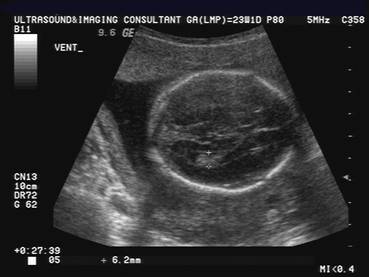

It is important to demonstrate normal cranial ossification (this differentiates this from osteogenesis imperfecta).